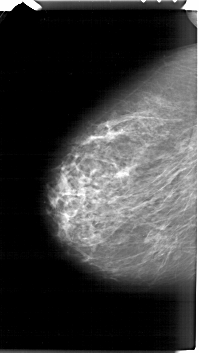

A_1485_1.LEFT_MLO

LEFT_MLO LINES 6676 PIXELS_PER_LINE 3826 BITS_PER_PIXEL 12 RESOLUTION 43.5 NON_OVERLAY